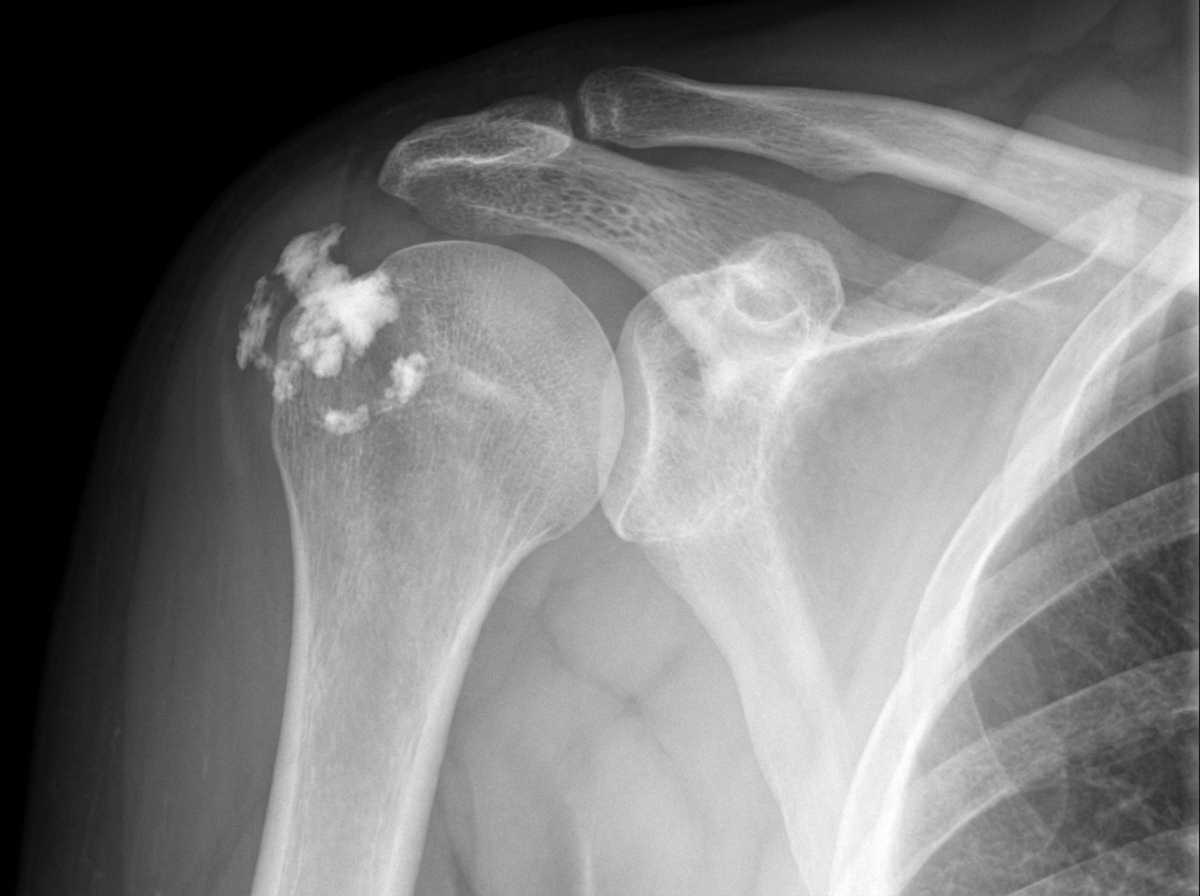

In a patient presenting with shoulder pain and no clear history of trauma, what does this radiograph most likely suggest?

Explanation: ***Calcific tendinitis*** - Radiograph shows **calcium deposits** within the **supraspinatus tendon** or other rotator cuff tendons, appearing as dense white opacities near the greater tuberosity. - Clinical presentation of **shoulder pain without trauma** is characteristic, often with **night pain** and restricted range of motion. *Shoulder dislocation* - Would show **loss of normal humeral head-glenoid relationship** with the humeral head positioned anteriorly, posteriorly, or inferiorly relative to the glenoid fossa. - Typically presents with **severe pain**, **inability to move the arm**, and obvious deformity following trauma. *Acromioclavicular dislocation* - Radiograph would demonstrate **separation** or **step-off** between the **acromion** and **distal clavicle** at the AC joint. - Usually results from **direct trauma** to the shoulder, such as a fall onto the lateral aspect of the shoulder. *Hill-Sachs lesion* - Appears as a **compression fracture** of the **posterolateral humeral head**, creating an indentation or flattening on the bone surface. - Associated with **anterior shoulder dislocation** and would require a history of significant trauma or recurrent dislocations.